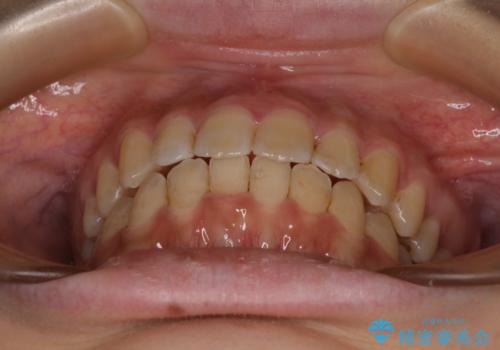

大学病院から転院 非抜歯で口元を下げるワイヤー矯正

- 大学病院にて装置を装着したものの、治療が十分に受けることができないとのことで転院をされた患者様です。

上顎歯列が前方にあり、口元が閉じにくくなっていたため、既に装着されている装置を使用して上顎歯列全体を後方に移動させていくこととしました。

舌の突出癖があり、それが原因で上下前歯に隙間ができていたため、改善のためのトレーニングを行うように指示をしました。